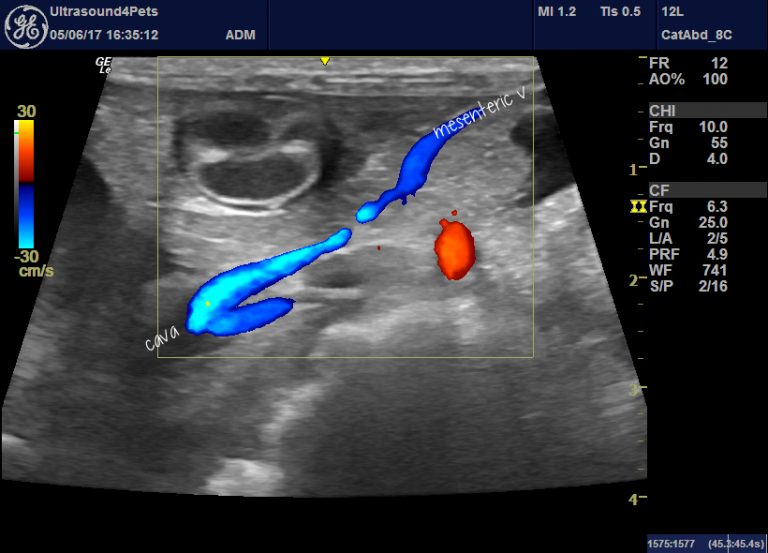

From members.sonopath.com

CT Extrahepatic Portosystemic Shunt in a 2 year old FS Chihuahua dog Extrahepatic Liver Shunt In Dogs Find out the ideal diet for pss patients, including energy, protein, vitamins, minerals, and amino acids. Learn about the causes, signs,. They can cause neurologic, urinary, and. portosystemic shunts (pss) are abnormal connections between the portal vein and the systemic circulation that bypass the liver. portosystemic shunts (pss) are abnormal connections between the portal vein and the vena. Extrahepatic Liver Shunt In Dogs.